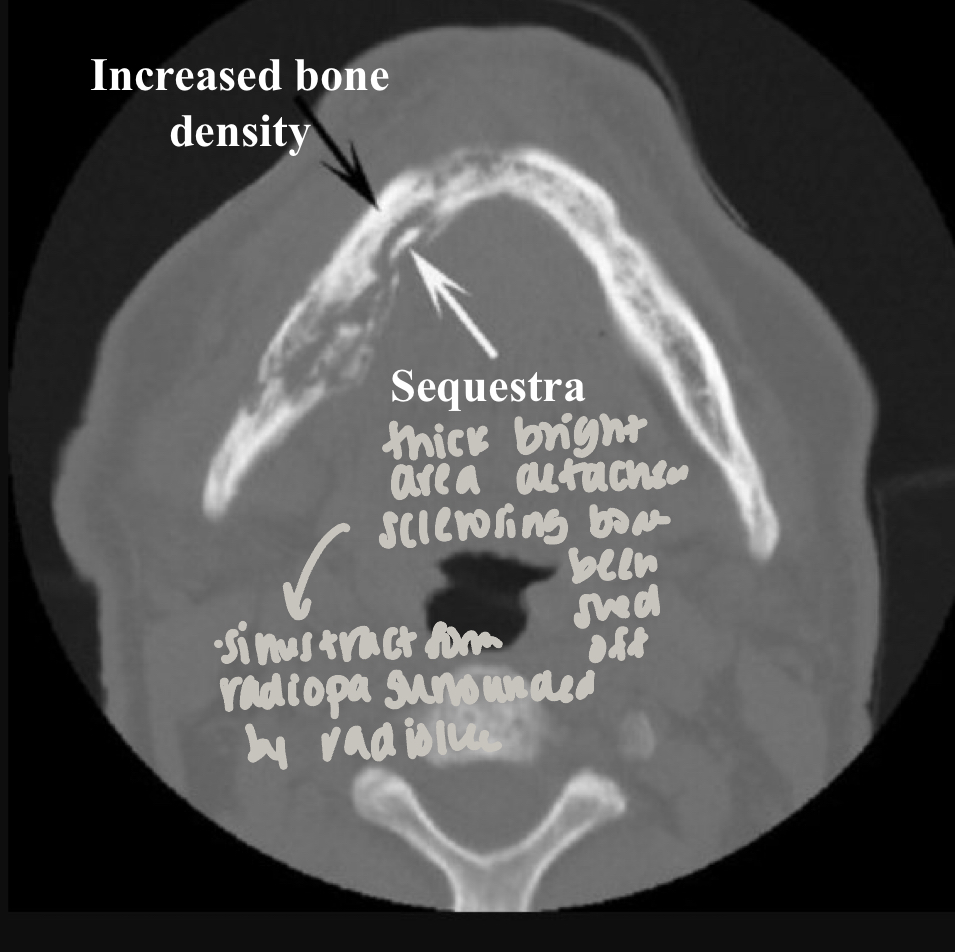

which imaging is method of choice for seeing internal structure (sequestrea) of acute osteomyelitis?

CT/CBCT

which type of chronic osteomyelitis?

primary response: proliferation reaction

sclerotic appearance of involved bone

subperiosteal bone deposition

slight jaw enlargement

involves large segment of jaw

diffuse sclerosing osteomyelitis

diffuse sclerosing osteomyelitis, young pt

diffuse sclerosing of left angle-ramus of mandible = L more radiopaque than R